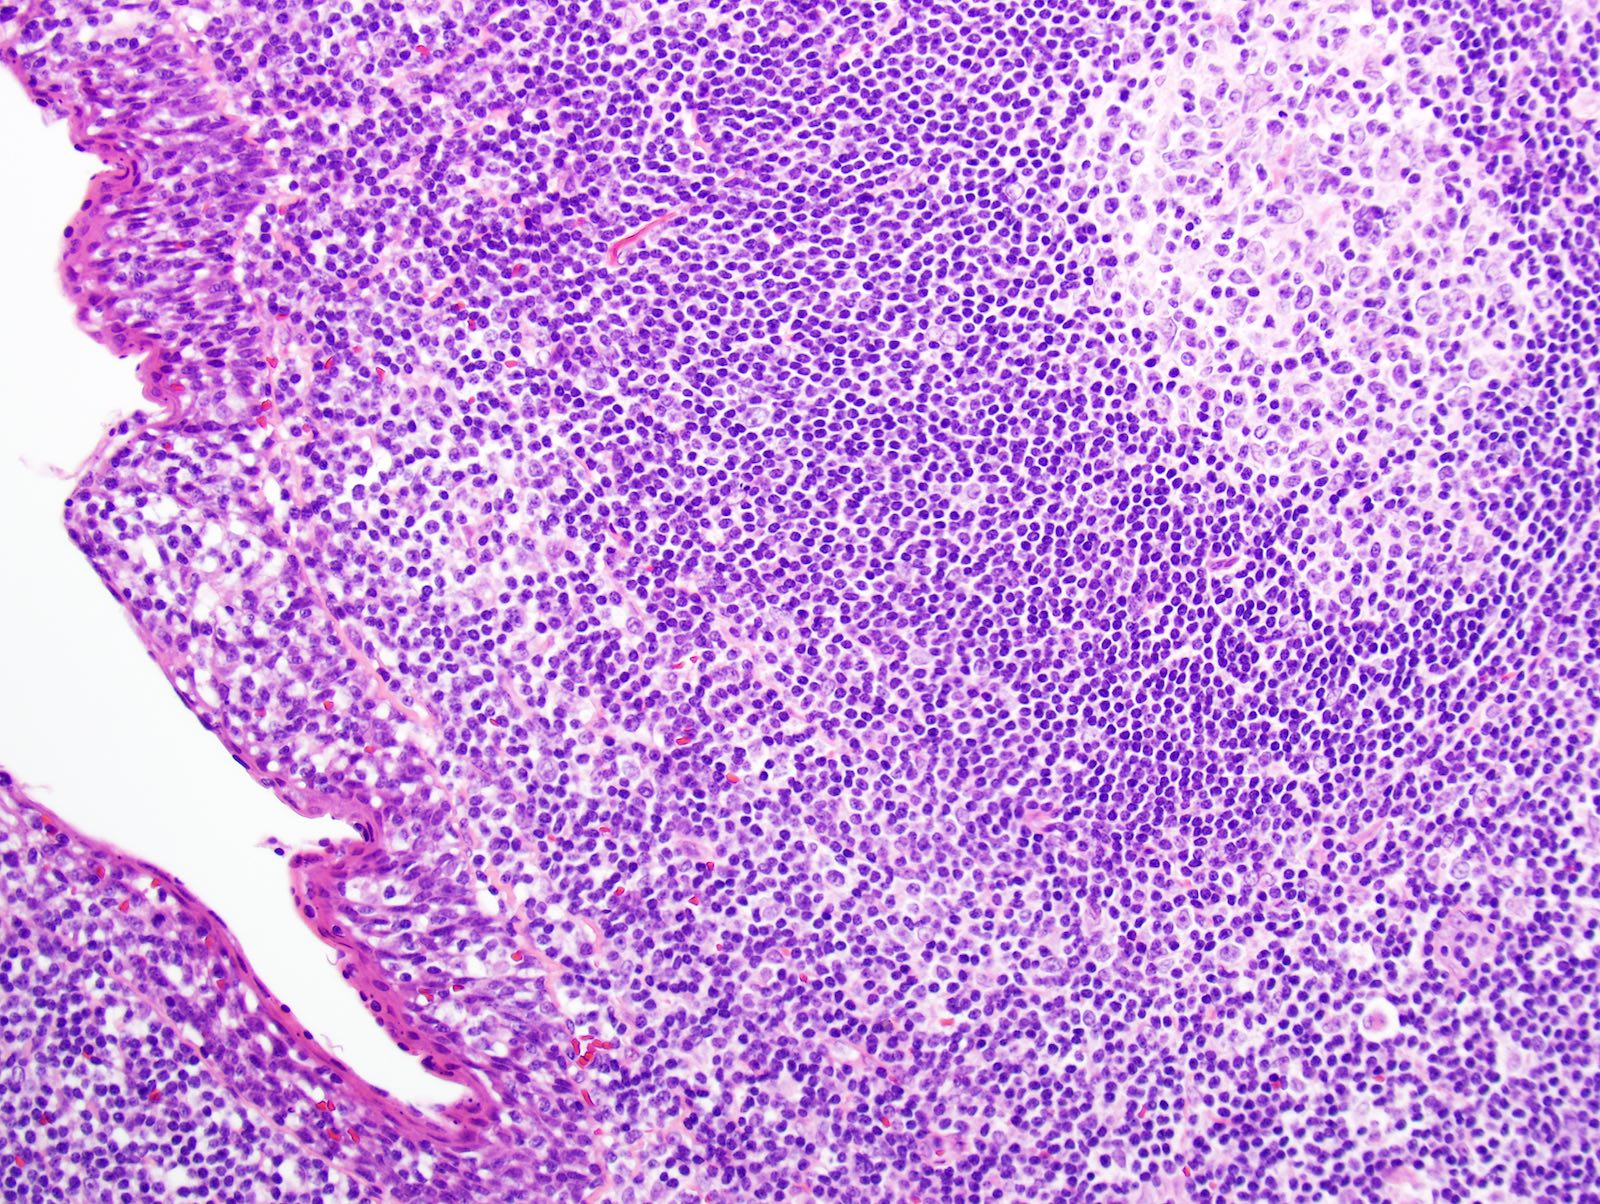

- Most cases show a unilocular cyst with a thin stratified squamous lining

- Epithelium is surrounded by dense polymorphous lymphoid tissue with germinal centers and sinusoidal spaces

- Lymphocytes frequently permeate the epithelial cyst lining cells

Microscopic (histologic) images